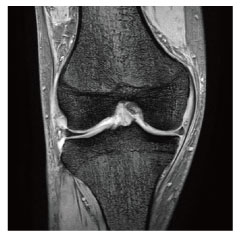

当院のMRI画像集